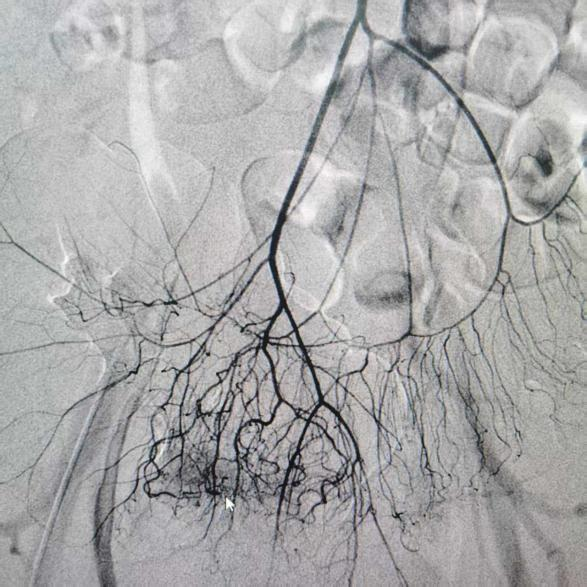

入院后检查显示,大肠及小肠末端肠腔存在大量暗红色血液及血凝块,此时患者血压已降至84/47mmHg、血红蛋白降至 69g/L,考虑持续活动性小肠出血伴失血性休克。在快速补液、止血输血的同时,消化内科连夜联系介入中心行急诊腹腔动脉造影及栓塞治疗。

术前胃肠镜、电子直肠和结肠镜检查结果

消化内科主治医师李思刚、副主任李雷兵,在介入中心主任罗阳指导下行腹腔动脉造影。他们精细操控微导丝,携微导管至出血的血管,予以明胶海绵颗粒进行栓塞,阻断异常血流。

术后造影显示靶血管血流截断,外溢征象完全消失,达到解剖性止血目标。

术前